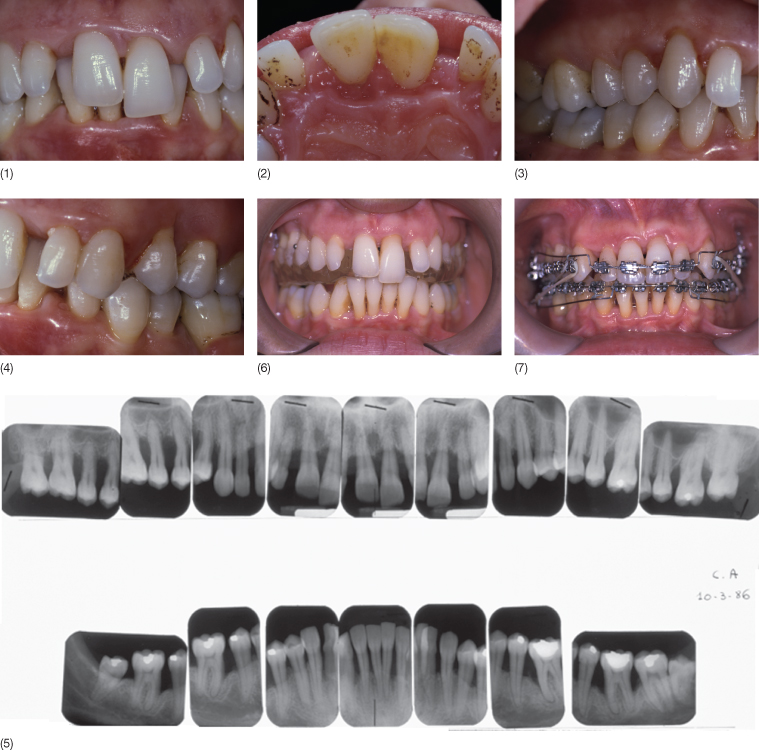

From www.intechopen.com

Figure 3. Orthodontic And Periodontic Orthodontics and periodontics are intricately linked since adult orthodontics often implicate the periodontium. The interaction between orthodontics and periodontics is both intriguing and complex. This literature review describes the damage situations and the methods of preventing and repairing them as well as situations in which the orthodontic intervention contributes to the periodontal. Orthodontic treatment of periodontal patients with a multidisciplinary. Orthodontic And Periodontic.